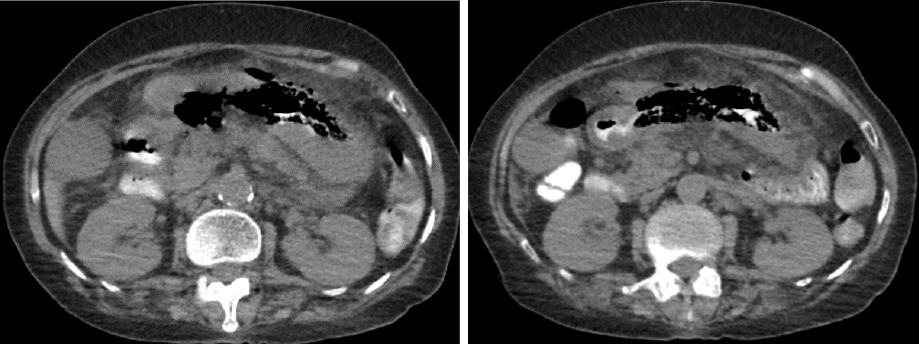

In April 2021, a 66-year-old female presented to our institute with shortness of breath, malaise, and sore throat. Upon presentation, she was drowsy and hypoxemic, with a respiratory rate of 24 breaths/minute and oxygen saturation of 55% on room air, a pulse rate of 84 beats/min, and blood pressure of 140/69 mmHg. After receiving 15 L/min of oxygen via a non-rebreather mask, her oxygen saturation improved to 92%. Her laboratory workup showed raised inflammatory markers (white cell count of 13.81 × 109/L, absolute neutrophil count of 10.6 × 109/L, and C-reactive protein of 269 mg/L), acute kidney injury (creatinine of 608 µ/L, potassium of 6.7 mmol/L, sodium of 126 mmol/L, urea of 23.1 mmol/L), normal hemoglobin (11 g/dL) and troponin T 28.4 ng/L, and liver function tests were unremarkable (alanine aminotransferaseof 34 IU/L, aspartate aminotransferase of 49 IU/L, and alkaline phosphataseof 185 IU/L). A semi-erect anteroposterior portable chest X-ray revealed bilateral infiltrates suggestive of COVID-19 pneumonia [Figure 1]. The patient tested positive for COVID-19 and was started on intravenous dexamethasone, ceftriaxone, frusemide, and gentle hydration. She was admitted with the impression of acute respiratory distress syndrome secondary to COVID-19.

Figure 1: A semi-erect anteroposterior portable chest X-Ray showing bilateral infiltrates, suggestive of COVID-19 pneumonia.